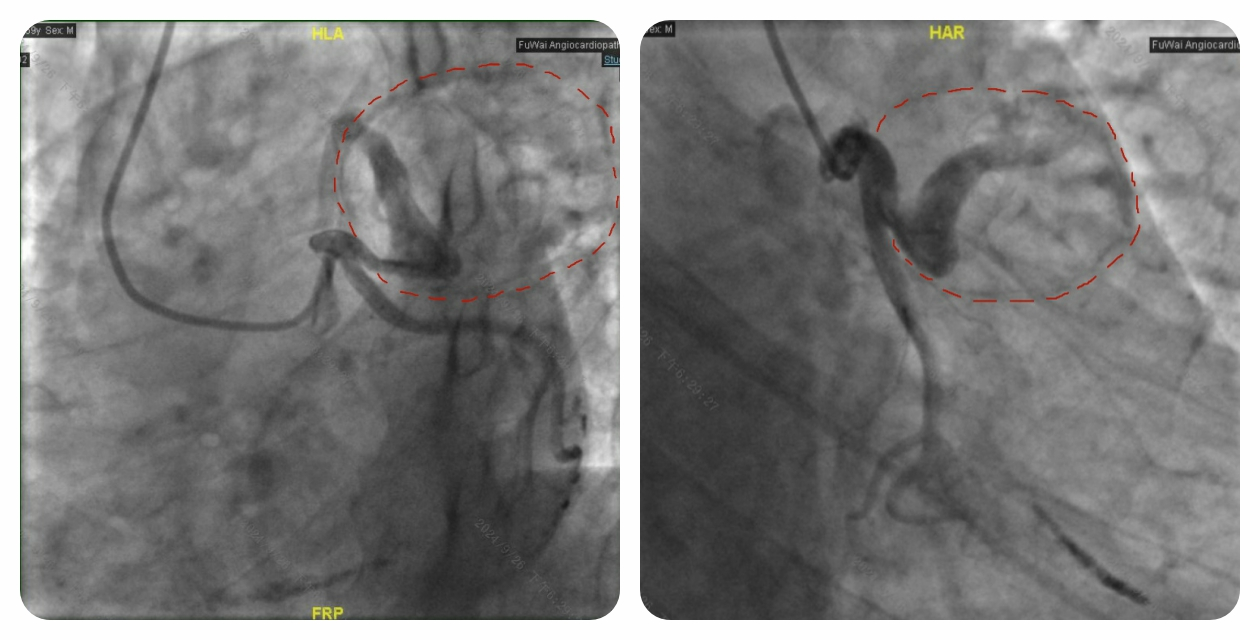

为了确定是否需要为老秦实施外科手术 “排雷”,我们紧接着安排了冠状动脉造影检查。结果显示,虽然冠状动脉前降支被 “地雷” 包裹,但血管腔依旧通畅,“地雷” 没有对冠状动脉造成压迫,血管内的血液也没有渗漏到 “地雷” 内。

经过手术专家们的深入讨论,一致认定老秦心脏上的 “地雷” 属于冠状动脉假性动脉瘤。由于 “地雷” 没有压迫冠状动脉,血液没有外溢,且表面有 “铠甲” 保护,内部又是实心血栓,爆炸风险相对较低。综合考虑老秦的意见后,专家团队决定暂不进行外科 “排雷”,而是建议他定期复查,密切关注 “地雷” 的动态。